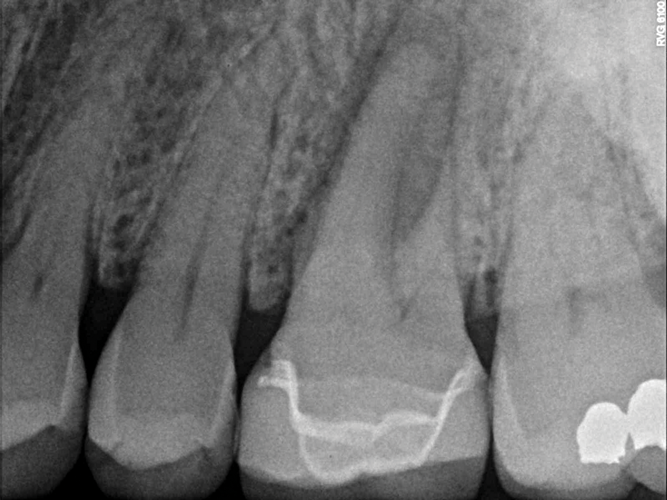

Fig 2. This penicillin-allergic patient presented with facial swelling secondary to pulpal necrosis with acute apical abscess on tooth No. 14 (Fig 2 and Fig 3). The swelling was consistent with cellulitis, thus systemic antibiotics were indicated in addition to definitive treatment by nonsurgical root canal therapy (Fig 4). Prior to 2019, clindamycin would have been the drug of choice, but newer guidelines warranted first-line use of cephalexin instead.10 Treatment in this case was initiated concurrently with antibiotic prescription and completed over two visits with the use of interappointment, intracanal calcium hydroxide. The infection resolved after treatment without complication.

Fig 3. This penicillin-allergic patient presented with facial swelling secondary to pulpal necrosis with acute apical abscess on tooth No. 14 (Fig 2 and Fig 3). The swelling was consistent with cellulitis, thus systemic antibiotics were indicated in addition to definitive treatment by nonsurgical root canal therapy (Fig 4). Prior to 2019, clindamycin would have been the drug of choice, but newer guidelines warranted first-line use of cephalexin instead.10 Treatment in this case was initiated concurrently with antibiotic prescription and completed over two visits with the use of interappointment, intracanal calcium hydroxide. The infection resolved after treatment without complication.